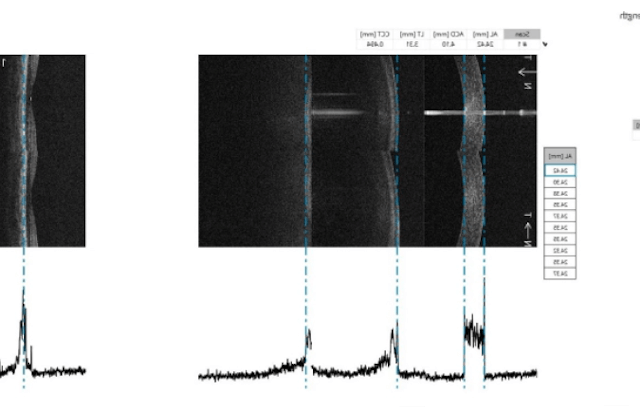

Orthokeratology is an optical method of myopia control management which is abbreviated as

Ortho-K. It is a method of vision correction using contact lenses made specifically for wearing

at night while you sleep. A secure, non-invasive process that improves eyesight clarity by

subtly altering the eye's surface curvature. Without the need of glasses or contact lenses for

the day, you can wake up with clear eyesight.

Ortho-K lenses for corneal reshaping are worn at night to rectify and restore eyesight clarity.